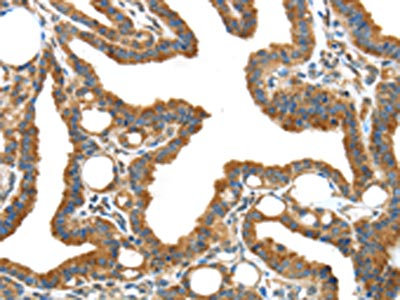

The image on the left is immunohistochemistry of paraffin-embedded Human thyroid cancer tissue using CSB-PA824414(IGFBP3 Antibody) at dilution 1/40, on the right is treated with synthetic peptide. (Original magnification: ×200)